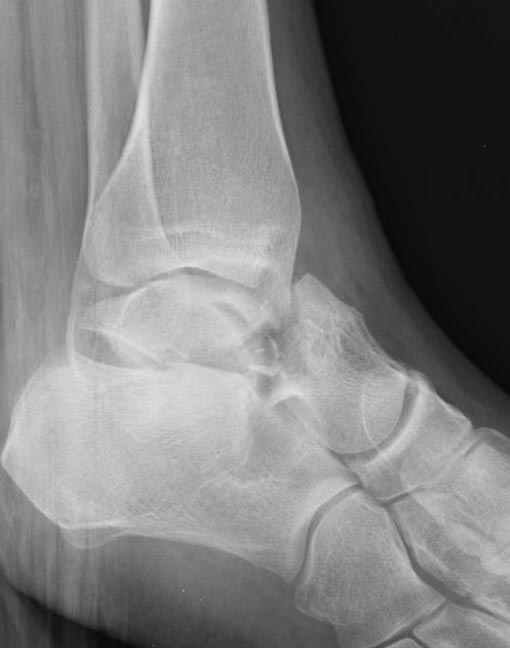

За пару недель насчитал 5 больных с переломом таранной кости, из них двое с двусторонним повреждением.

Из-за отека на стопе тактика лечения у всех была

одинаковая: временная наружная фиксация до спадения отека, при изолированных переломах они выписывались домой и через дней 7 госпитализировались на оперативное лечение.

Примеры на снимке...